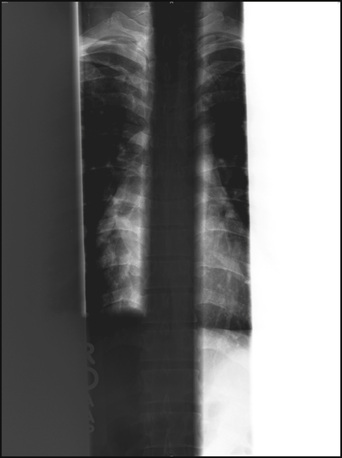

If multiple fields are projected onto a single IP, each must have clear, collimated edges and margins between each field. This process, called partitioning, allows two or more images to be projected on a single IP. Figure 21-19 illustrates the opposite situation.

The cause of these collimation artifacts is vendor algorithm related. The exposure field recognition algorithm is unable to match image histograms if the fields are not clear. This algorithm is based on edge detection or area detection. Further postprocessing of each image requires digital data representative of anatomy—not twice-irradiated or unirradiated portions of the IP.